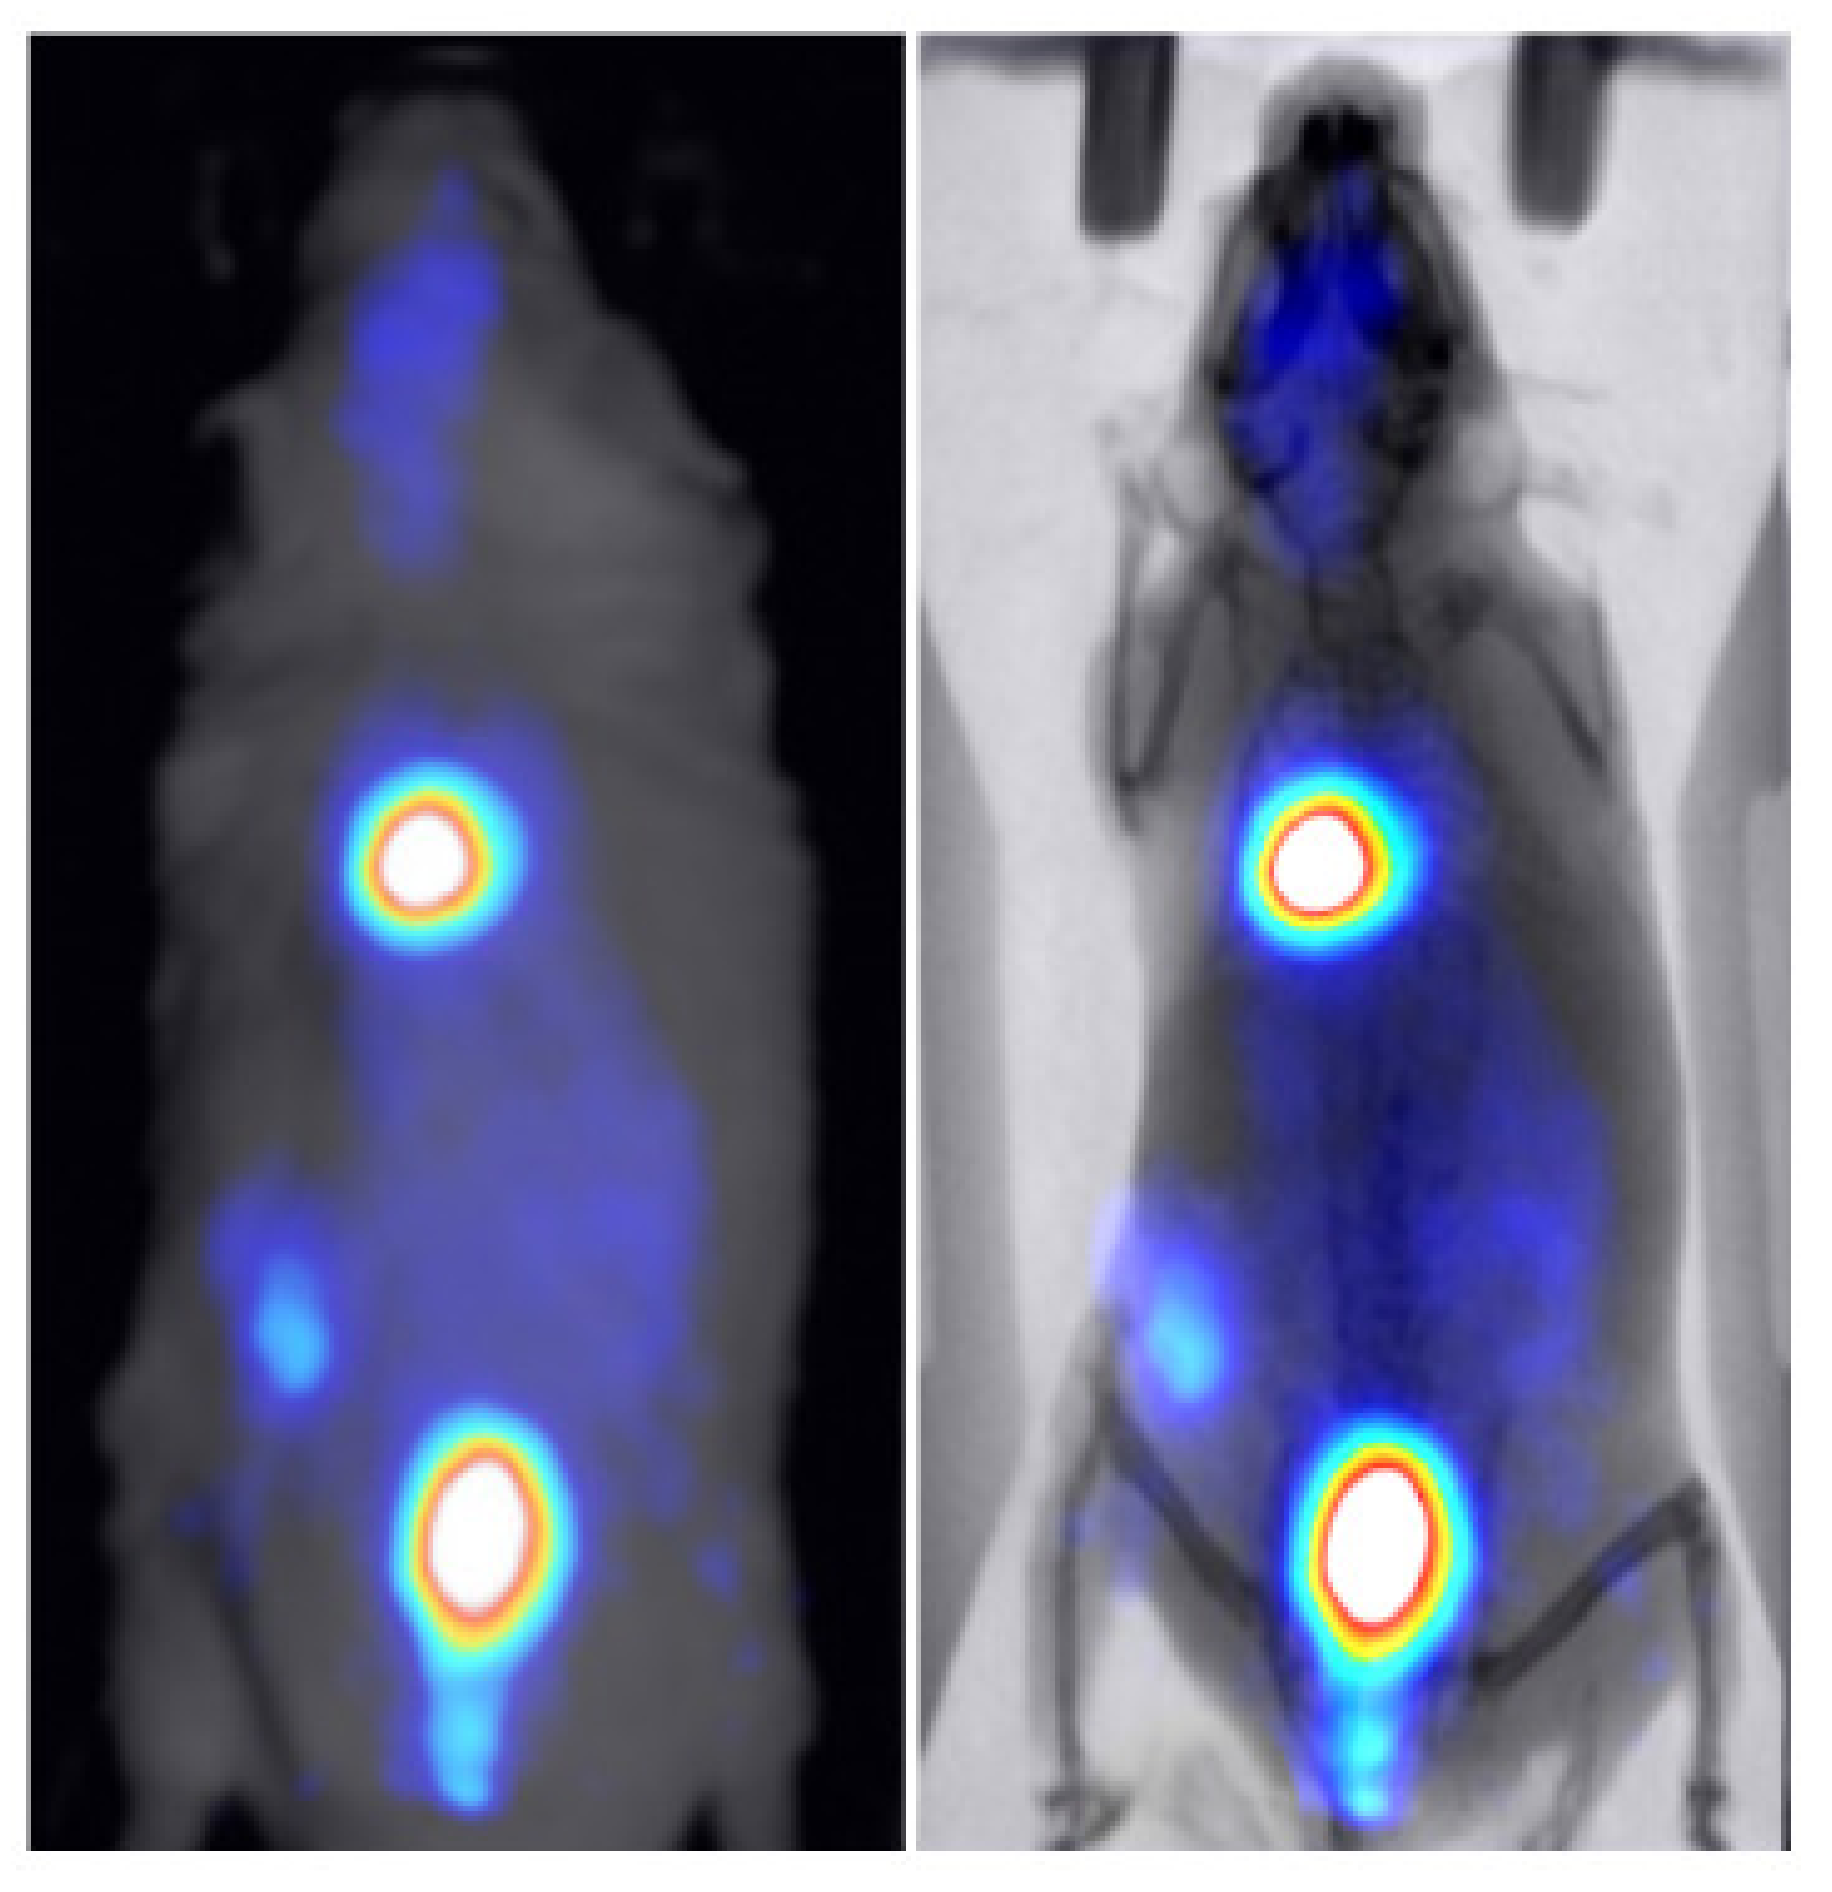

3.2. Animal Mapping during In Vivo Molecular Imaging Experiments